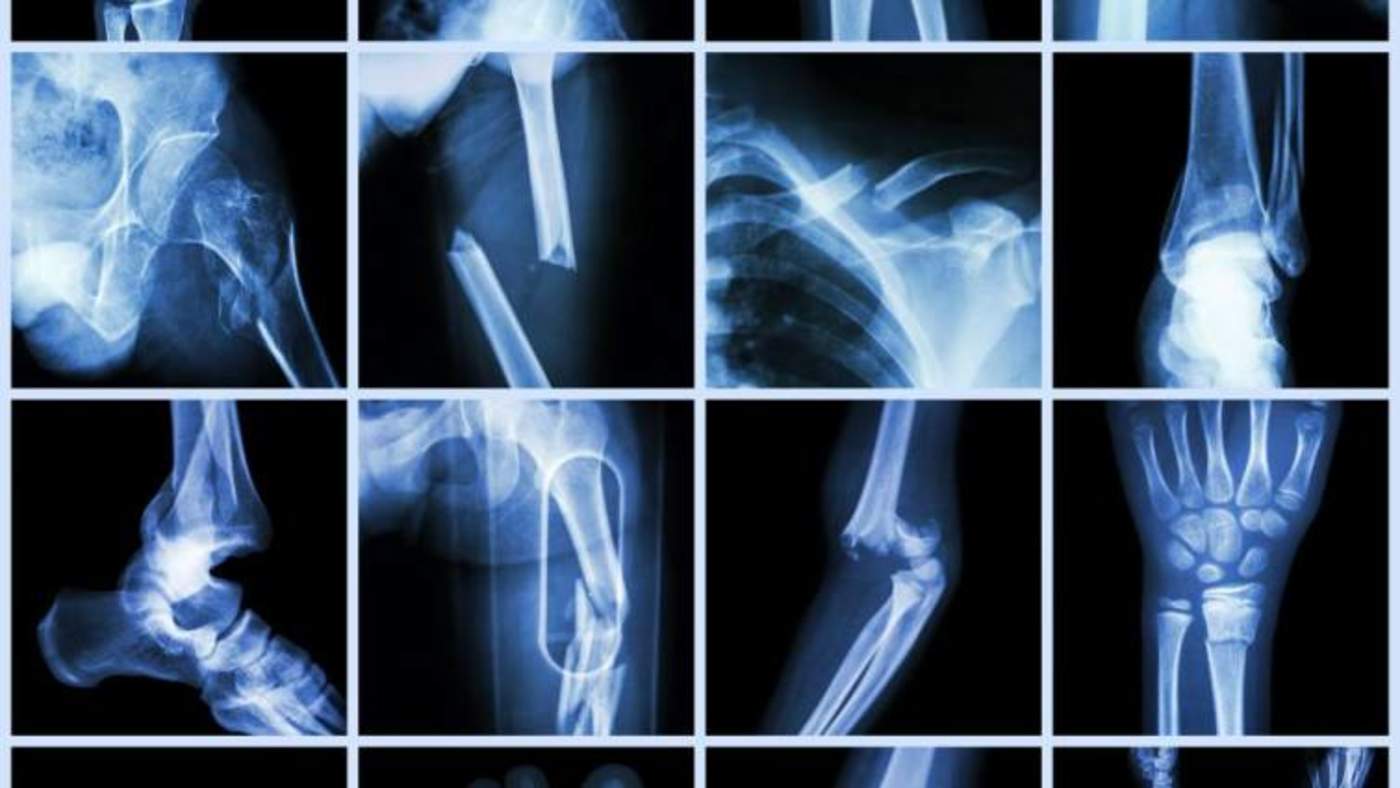

Los huesos son órganos muy duros y aún así poseen una malla estrecha de vasos sanguíneos en su cavidad interna donde se encuentra la médula ósea, mientras que la superficie de la estructura ósea también está cubierta por el periostio vascularizado.

Como cualquier otro órgano, explicaron, los huesos necesitan un circuito circulatorio cerrado (CCL) para funcionar correctamente. Este sistema libera sangre fresca a través de las arterias hacia el hueso, y hasta ahora era un proceso del que no se conocía en su totalidad.

Anika Grüneboom, del Hospital Universitario de Erlangen y una de las científicas participantes en la investigación, explicó que en estudios realizados en los huesos largos de los ratones, el equipo observó y caracterizó un nuevo tipo de capilar que, de manera perpendicular al eje largo, atraviesa todo el hueso duro.

Esos nuevos vasos sanguíneos se denominaron "vasos transcorticales" (TCV, por sus siglas en inglés), y pueden ser de origen arterial o venoso.

Informaron que una línea de investigación futura podría ser el papel que desempeñan los vasos transcorticales en la fisiología ósea y su relación con enfermedades como la osteoporosis, la artritis reumatoide o tumores en los huesos.